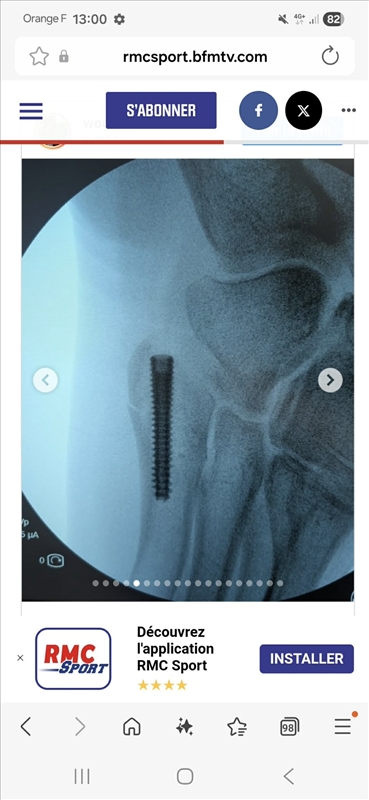

rody83 No pain, no gain | En effet, pas grand chose à voir avec la cheville... d'ailleurs ça me rappelle (toutes proportions gardées, dans mon cas c'était un membre supérieur) ce que je suis fait à la main y'a un an (= broche dans la tête de M5). Par contre il y a fort à parier qu'il lui faudra repasser sur le billard pour enlever la vis... avec une petite indispo associée. Message édité par rody83 le 13-01-2026 à 15:05:06 --------------- .: Passions | Galerie | Blog :. |

Monkira | Il y a une photo de sa cheville ( sur son strava ?) qui est énormément gonflée également donc la cheville a du être touchée quand même ( peut être pas de fracture par contre). |